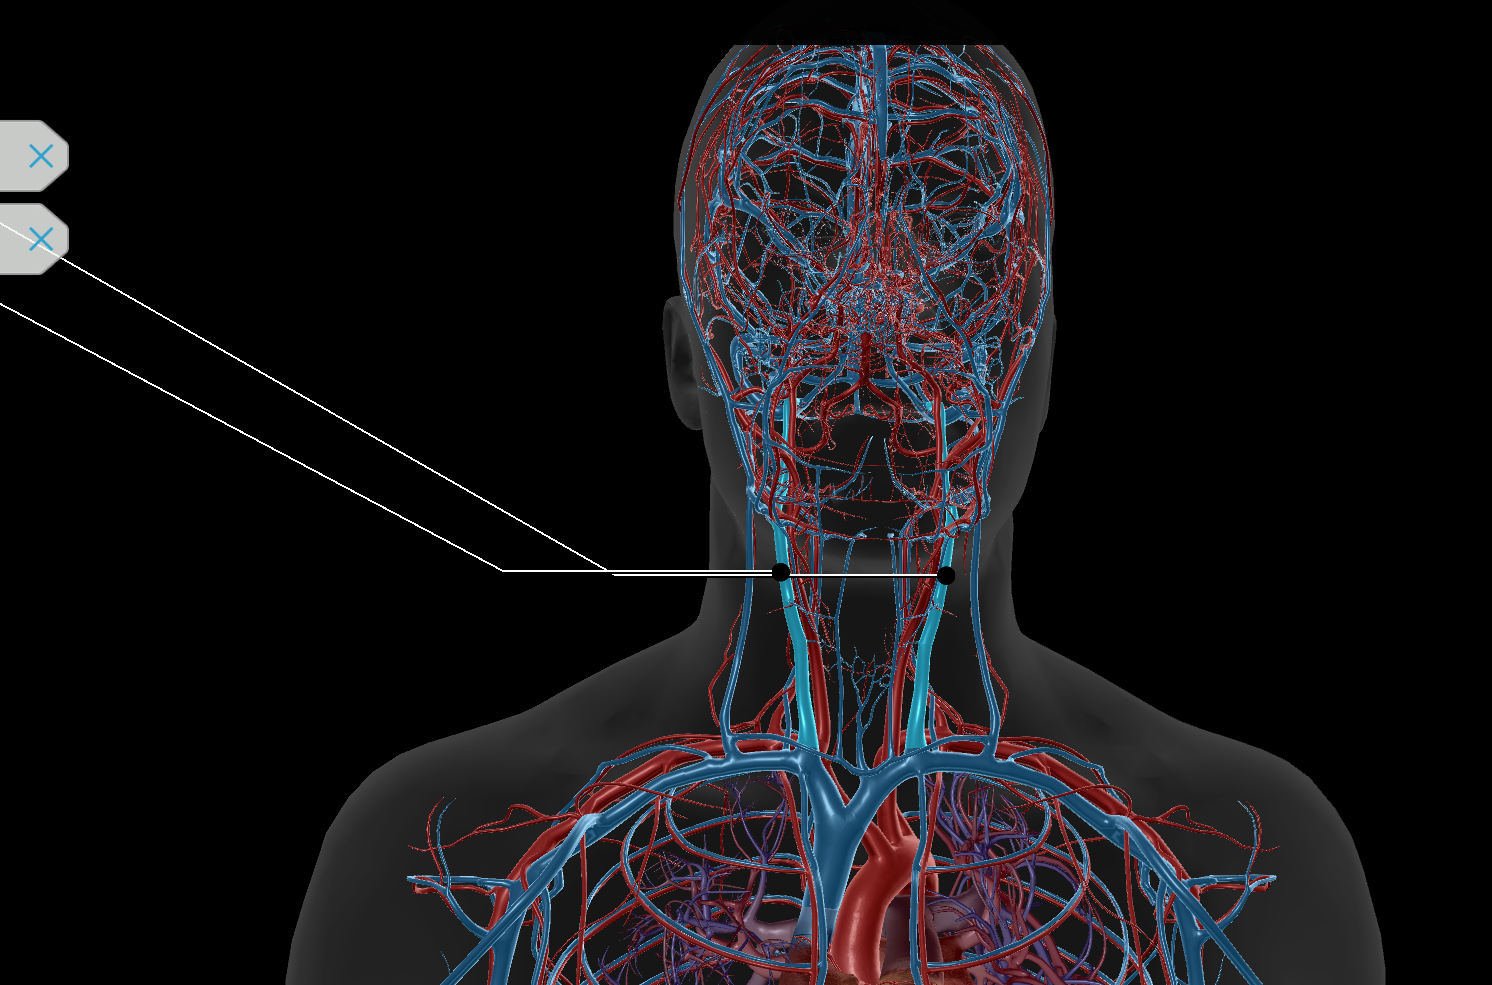

Common Carotid Artery

Internal Jugular Vein

External Jugular Vein

Brachiocephalic Vein